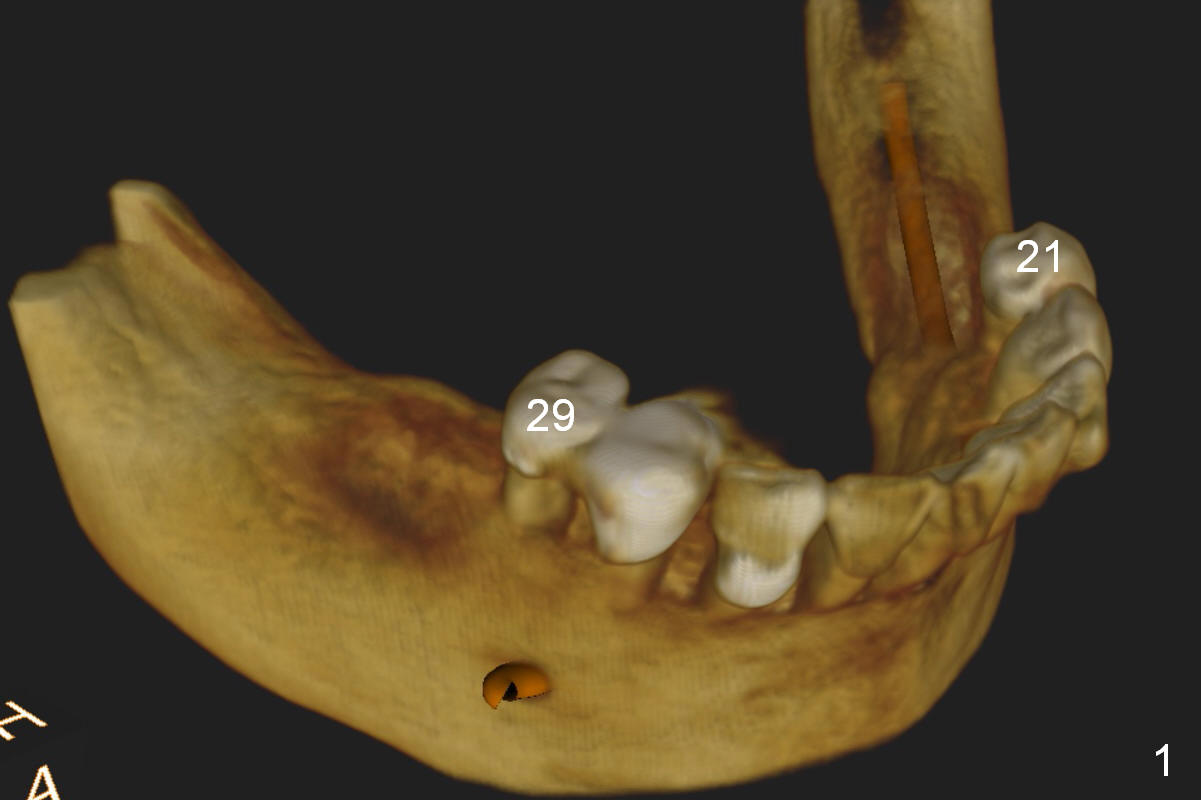

A 52-year-old lady has lost 5 lower posterior teeth (Fig.1 CBCT 3D image), which are restored by quadrant (LL).

Fig.2 (sagitttal section) shows that the bone height at the site of #31 is shorter than that of #30. There is a 1 mm separation from the Inferior Alveolar Nerve (brown) if a 8 mm implant is placed at #31 (Fig.2,3 (coronal section)), whereas 3 mm separation for a 6 mm implant (Fig.4). Since the tooth #2 is supraerupted, the shorter implant at #31 is more appropriate. It is placed a little deeper (Fig.4' arrow) so that the abutment or the opposing tooth does not need to be trimmed too much. In addition, choose a widest abutment (purple, e.g., 7.8 mm) with the shortest cuff (pink, 1 mm). A splinted immediate provisional will be fabricated to prevent the gingiva from growing into the abutment margin. At restorative phase, a smaller abutment will be used (e.g., 5.8 mm) so that the gingiva is clear from the margin. It will be easy for impression. Then the provisional will be relined to keep the gingiva from growing into the space just created by changing abutments. Bone graft will be needed buccal to the implant at #31 (Fig.3,4 red circle; L: lingual).